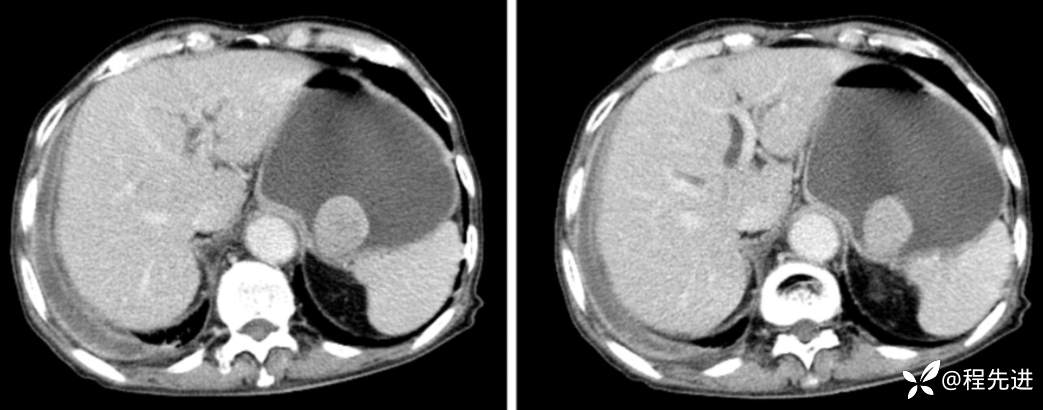

门脉期

延迟期